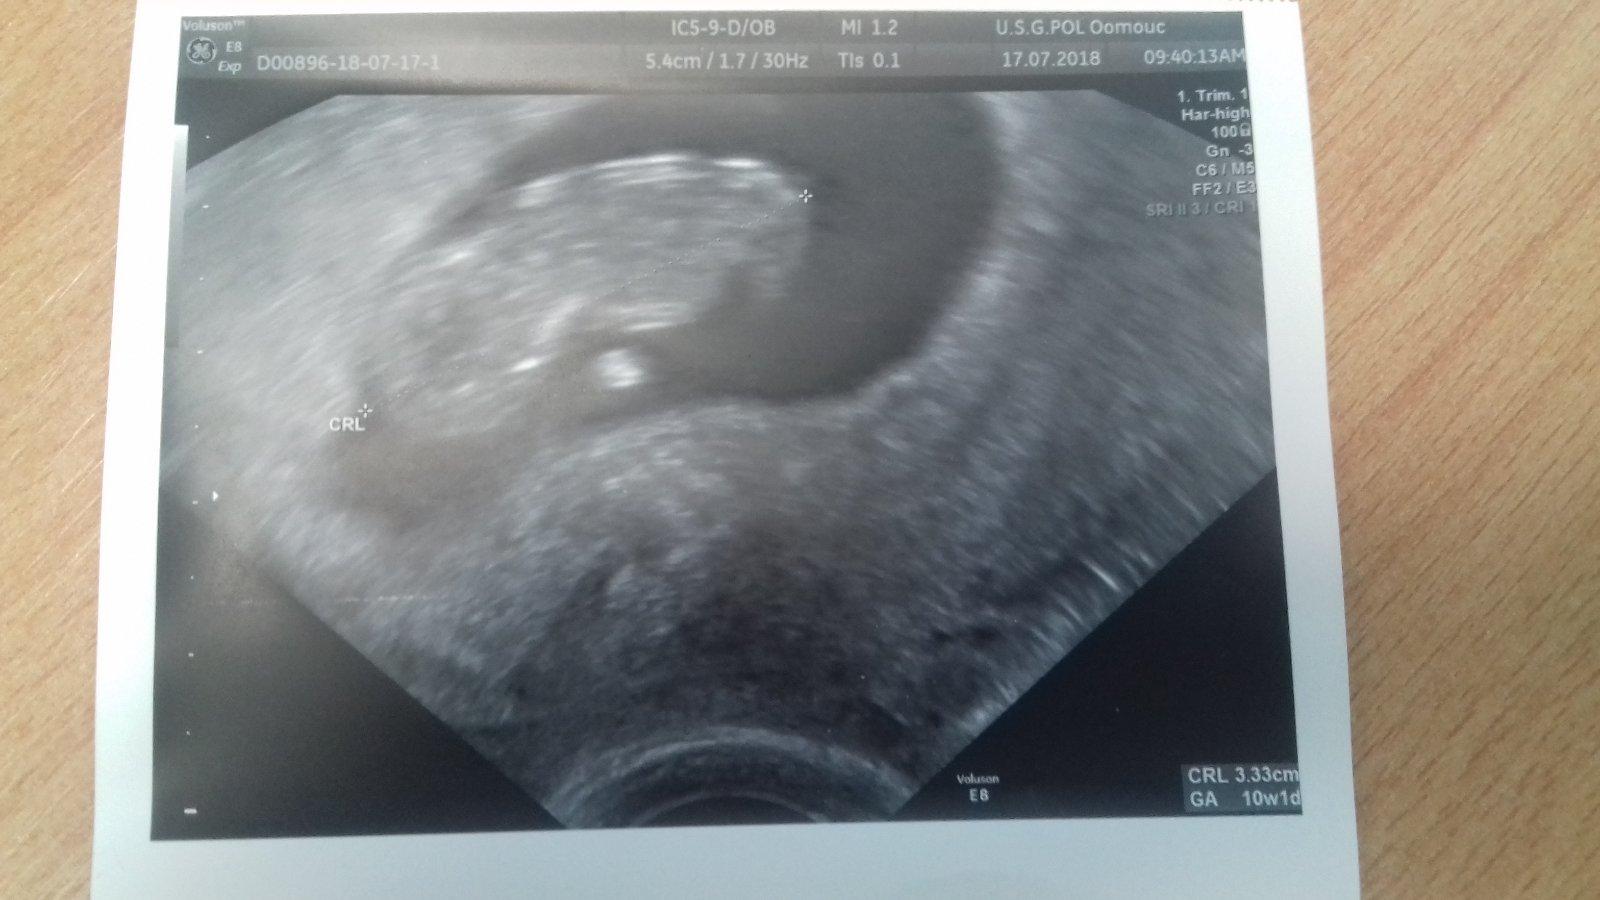

@jednaholkaa já jsem letěla teď v 9+3 a za 4 dny zpátky. Měla jsem obavy a kdyby už to nebylo zaplacené a jen let 1:45 tak neletim. Ale zvládla jsem to a dneska na utz je miminko v pořádku,je i o pár dní větší než podle ovulace.( Ale hrozně sebou mlelo,tak se to dalo těžko zaměřit)

Ahoj holky, pokud muzu pridam se k Vam, dnes dle ultrazvuku jsem 10+2 jen me ted vydesila kamaradka ze ji uz se v tomto tt dite na obrazovce hybalo a ja jsem nepozorovala pohyb zadny, je mozne ze jsou ruzne ultrazvuky jebo jak si to vysvetlit?

@jancaluba Šmankote šmankote, na tyhle porovnávačky se vyprdni. Kdyby něco nebylo v pořádku dr by si toho jistě všiml. Ultrazvuky jsou opravdu různě kvalitní. Koukni na svojí fotku a na fotku, co dávala kolegyně o stránku dřív. Buď v klidu. Vítám tě mezi námi. 😌

@jancaluba presne jak pise vilmic, kdyby bylo cokoliv spatne dr.by Ti rekl/a,ja taky zadny pohyb nevidela, krom tlukouciho srdicka, zalezi na UTZ si myslim